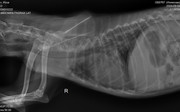

Коллапс трахеи форум